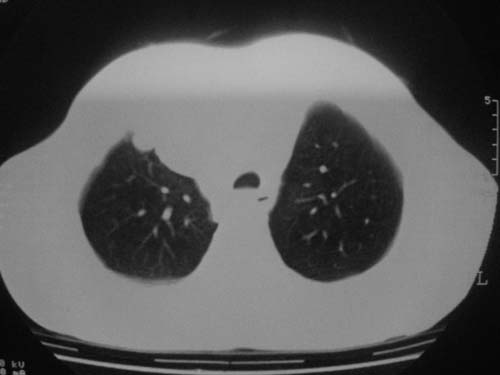

以下是引用科室第一人在2010-3-25 20:30:00的发言:[br]1:纵膈肿瘤性病变,恶性胸腺瘤可能性大伴纵膈右肺门淋巴结转移,右侧胸腔积液。[br]2:右侧肺门肿瘤性病变,纵膈淋巴结转移,右侧胸腔积液。右下叶转移。

以下是引用子期在2010-3-25 21:00:00的发言:[br]先考虑右中央型肺癌伴转移。

以下是引用江广1996在2010-3-25 22:49:00的发言:[br]通常肺癌向纵隔转移多见,纵隔肿瘤向肺内转移少见(有的表现为向肺内侵润)。本例以一元论考虑:右中心型肺癌并纵隔淋巴等多处转移。[br][br][本贴已被 江广1996 于 2010-3-25 22:50:07 修改过]

以下是引用yangyudong333在2010-3-26 6:43:00的发言:[br]“冰冻纵膈”,考虑纵膈淋巴瘤伴肺内及胸膜侵润。